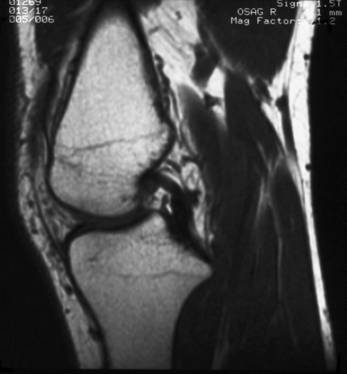

Rezonanta magnetica nucleara

RMN poate fi considerata actualmente ca metoda optima de explorare a genunchiului (fig. 12a, b). Neinvaziva si netraumatica, ea constituie cel putin deocamdata o cale inegalabila de diagnostic in patologia reumatologica, ortopedica si oncologica. Corticala osoasa emite un semnal de joasa intensitate si apare sub forma unei structuri lineare negre ce contrasteaza cu semnalul intens al structurilor vecine (spongioasa osoasa si grasimea periarticulara). Medulara osoasa prezinta un semnal intens datorita continutului sau grasos; jonctiunea metafizo-epifizara apare la adult sub forma unei fine linii de hiposemnal. Cartilajul hialin articular emite un semnal de intensitate intermediara, spre deosebire de fibrocartilajul meniscal care apare in hiposemnal. Ligamentele, tendoanele si capsula articulara emit un semnal de slaba intensitate, distingandu-se de tesuturile grase vecine si de osul pe care se insera. Vasele sanguine apar in hiposemnal. Nervii prezinta un semnal ceva mai intens datorita continutului grasos al mielinei. Lichidul sinovial emite un semnal intermediar pe secventele ponderate in T1 si apare in hipersemnal pe secventele ponderate in T2.

Fig. 12a - Sectiune sagitala RMN la nivelul genunchiului

Fig. 12b - Sectiune axiala RMN la nivelul genunchiului